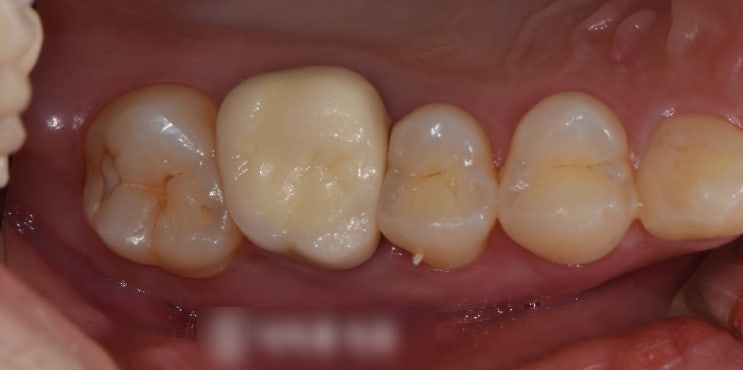

신촌역치과 정기검진의 중요성 다수의 충치 재발, 인레이, 신경치료

안녕하십니까, 대표원장 조민기입니다. 여러분들께서는 정기검진 을 받으신지 얼마나 되셨나요? 많은 분들...